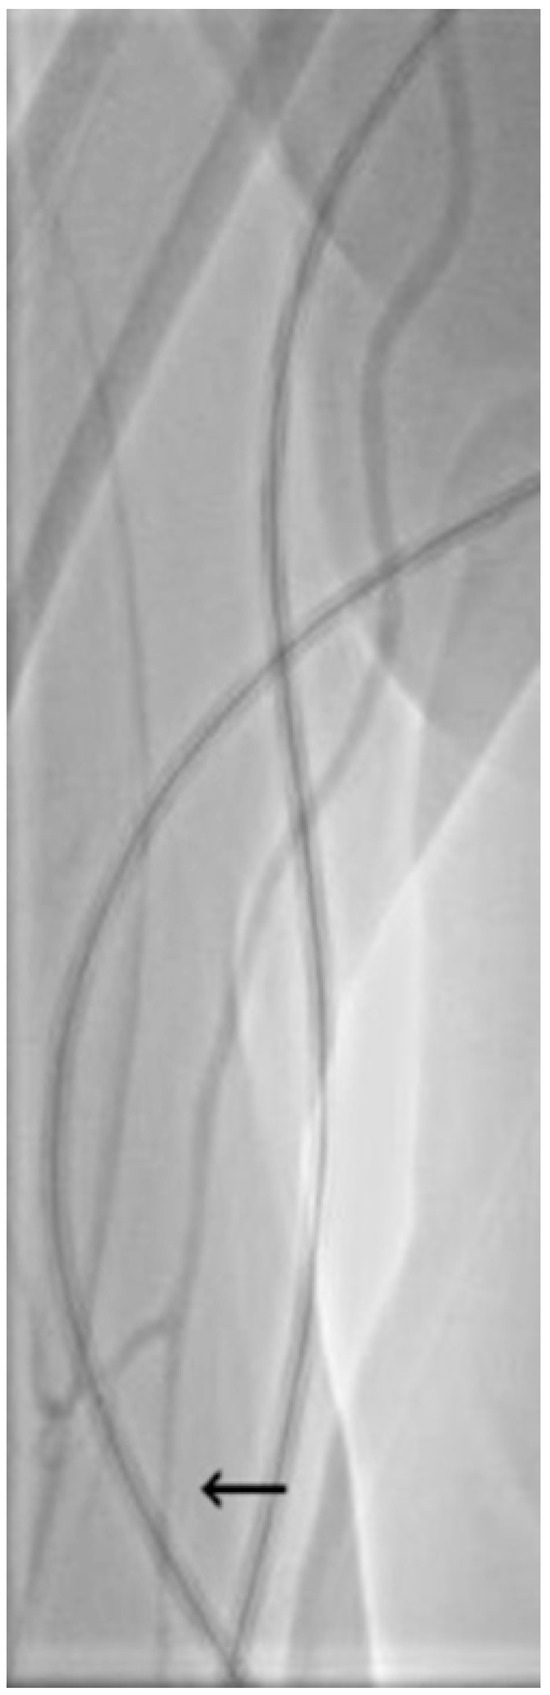

| Localized or diffuse spasm | Localized = 20/63 (31.7%) Diffuse = 43/63 (69.3%) |

| Radial artery spasm | 25/47 (53.2%) | 39/53 (73.6%) | p = 0.0349 |

| Localized or diffuse spasm | 12/25 localized (48.0%) 13/25 diffuse (52.0%) | 7/39 (17.9%) localized 32/39 diffuse (82.1%) | p = 0.0109 |